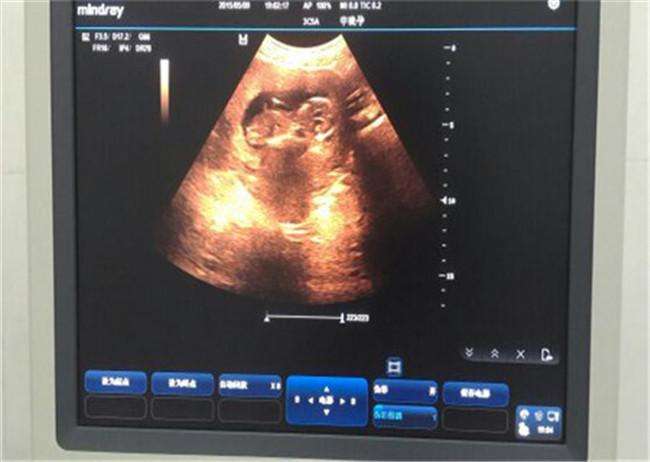

导语:怀孕三个月时,胎儿的身体还比较小,还可以在妈妈子宫里的羊水里游泳,不断变化姿势,所以姿势是并不固定的。有时候你看着他是趴着的,有时候他又有可能会转过来,在这个时期去拍检查NT排畸的图片,如果姿势不对,医生有可能会检查不到重点部位的发育情况。

三个月的胎儿怎么样让他把姿势转过来?转过来才能够检查看到看到胎儿的情况。

有时可能需要半小时到一小时才能转过体位来,然后再继续检查NT或者B超,我们要有耐心。